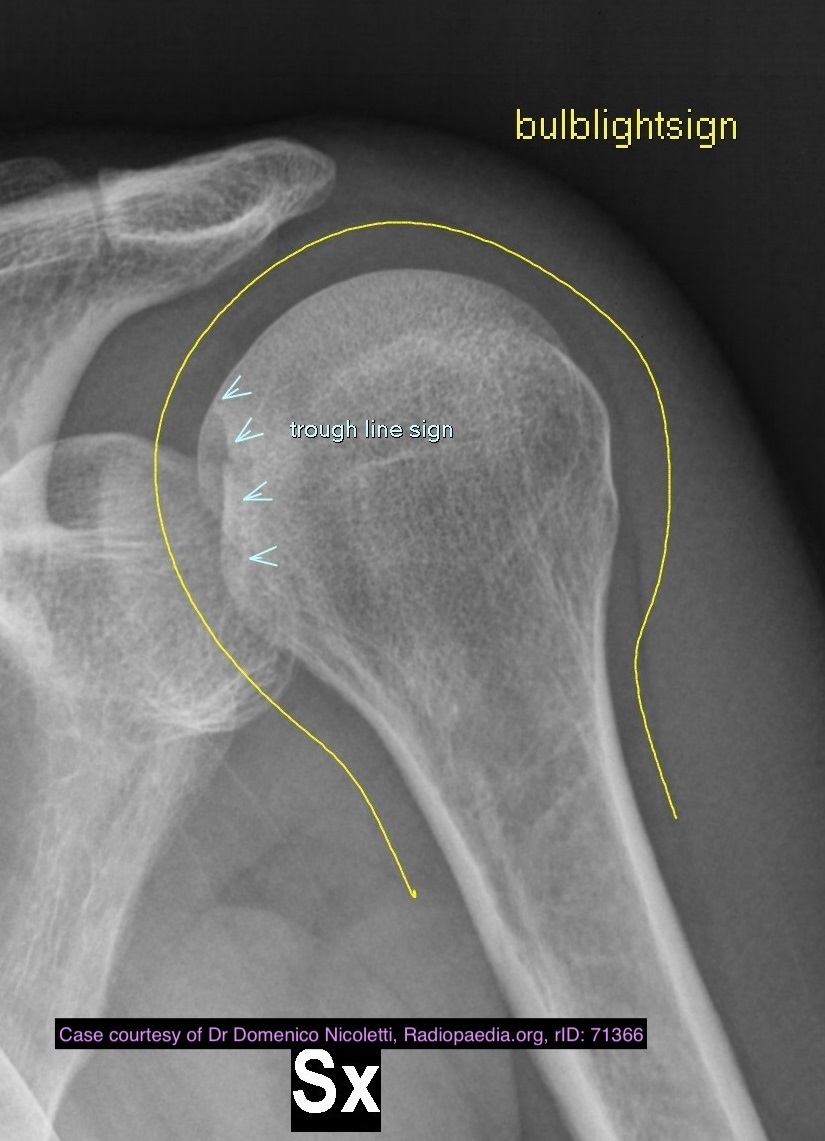

Posterior Dislocation

Dr Henry Knipe◉◈ and Radswiki◉ et al.

The trough line sign is a sign of posterior shoulder dislocation on AP shoulder radiograph.

Pathology

In a posterior dislocation, the anterior aspect of the humeral head becomes impacted against the posterior glenoid rim. With sufficient force, this causes a compression fracture on the anterior aspect of the humeral head. This compression fracture is analogous to the Hill-Sachs compression fracture seen with anterior shoulder dislocation of the glenohumeral joint.

Radiographic features

Plain radiograph

Frontal radiographs reveal two nearly parallel lines in the superomedial aspect of the humeral head.